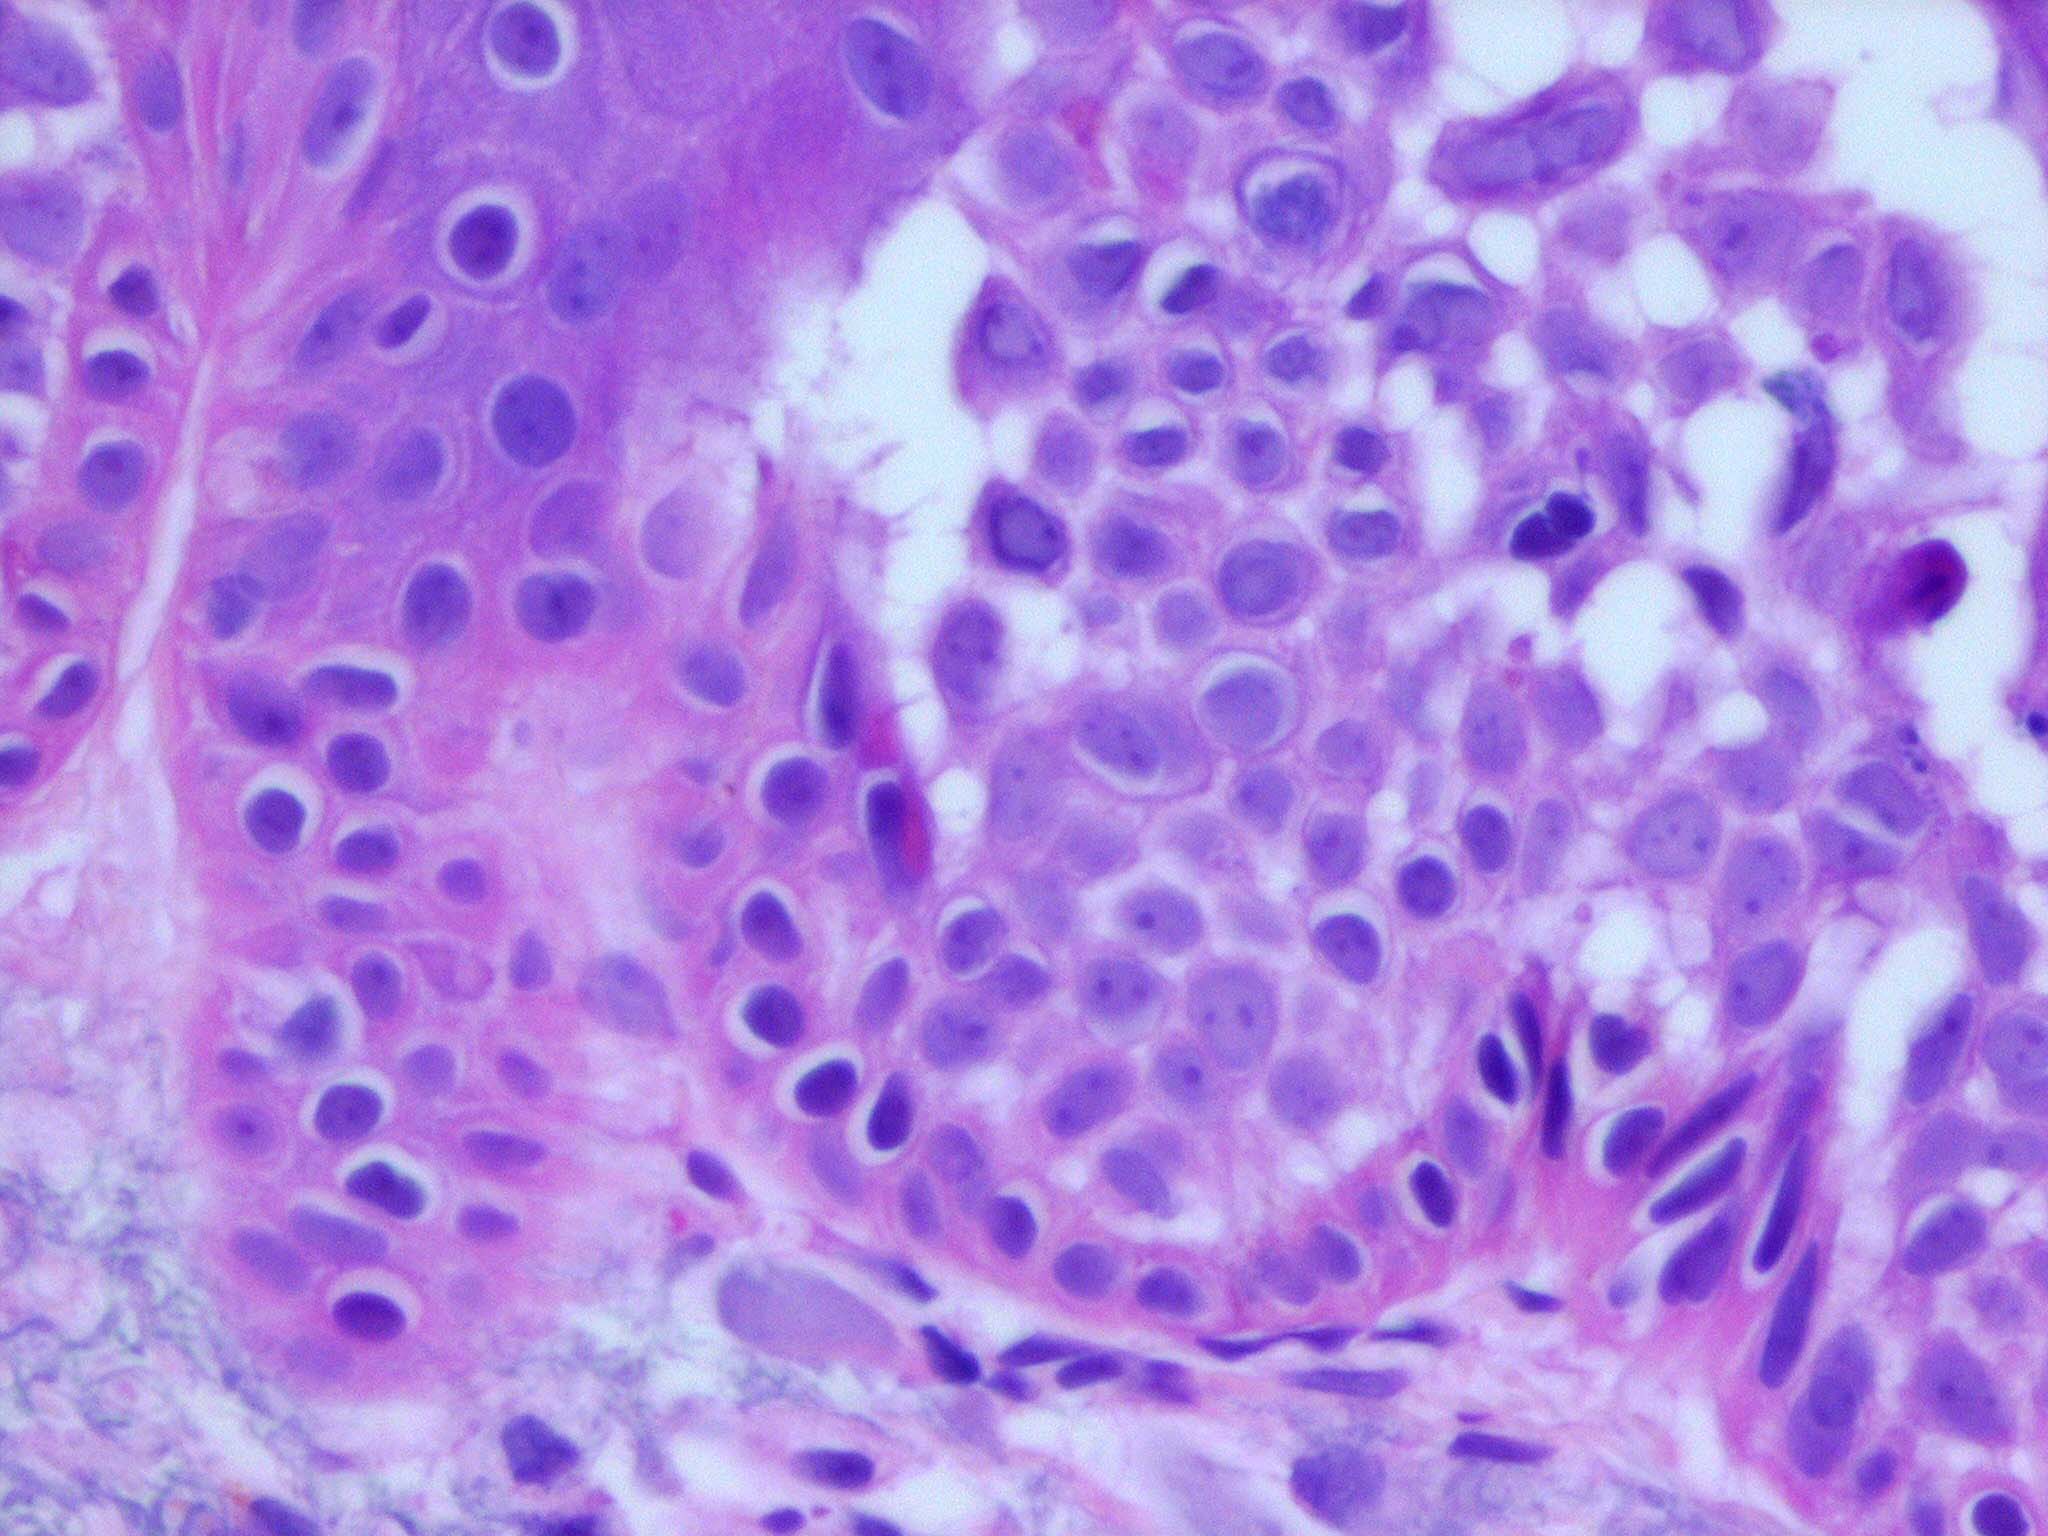

Bowen disease is a full-thickness anaplasia of the epidermis, with loss of the normal maturation of its components. Keratinocytes are atypical and disorderly, often described as having a windblown appearance. Although the basal cell layer is intact, extension of keratinocyte atypia down the follicular epithelium is seen. Vacuolization, mitoses, individually keratinizing cells, and multinucleated cells are present in the epidermis. Large pale keratinocytes with abundant ground-glass cytoplasm, so-called pagetoid cells, often are distributed haphazardly throughout the epidermis. Hyperkeratosis, parakeratosis, and acanthosis are seen to some degree in lesions of Bowen disease. The upper dermis has a moderate lymphocytic infiltrate.